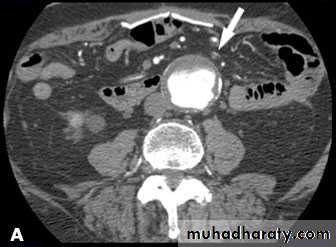

CT & CT angio of abdominal aortic aneurysm

Ruptured abdominal aortic aneurysm